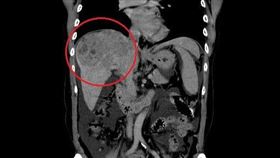

七旬嬤腹痛誤認腸胃炎 竟是晚期肝癌

70歲嬤腹痛險暈倒田中 檢查才知晚期肝癌 70歲...